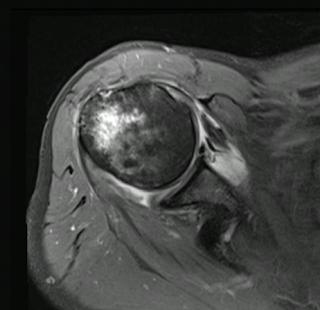

and these MRI's